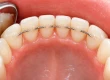

The “3 on 6” model is a modern implant solution designed to replace all teeth in either the upper or lower arch using six individual dental implants to support three separate bridges. This stands in contrast to All-on-4 systems, which typically use four implants and a single monolithic prosthetic.

Each bridge is supported by two implants, providing a modular and natural-feeling structure that mimics the biomechanics of natural teeth more closely. This segmentation improves functionality, oral hygiene, and overall comfort.

- Improved Oral Hygiene: Spaces between bridges allow easier cleaning compared to a monolithic denture.

- No Artificial Gums: Unlike All-on-4, this technique typically avoids fake gum material, offering a more natural look.